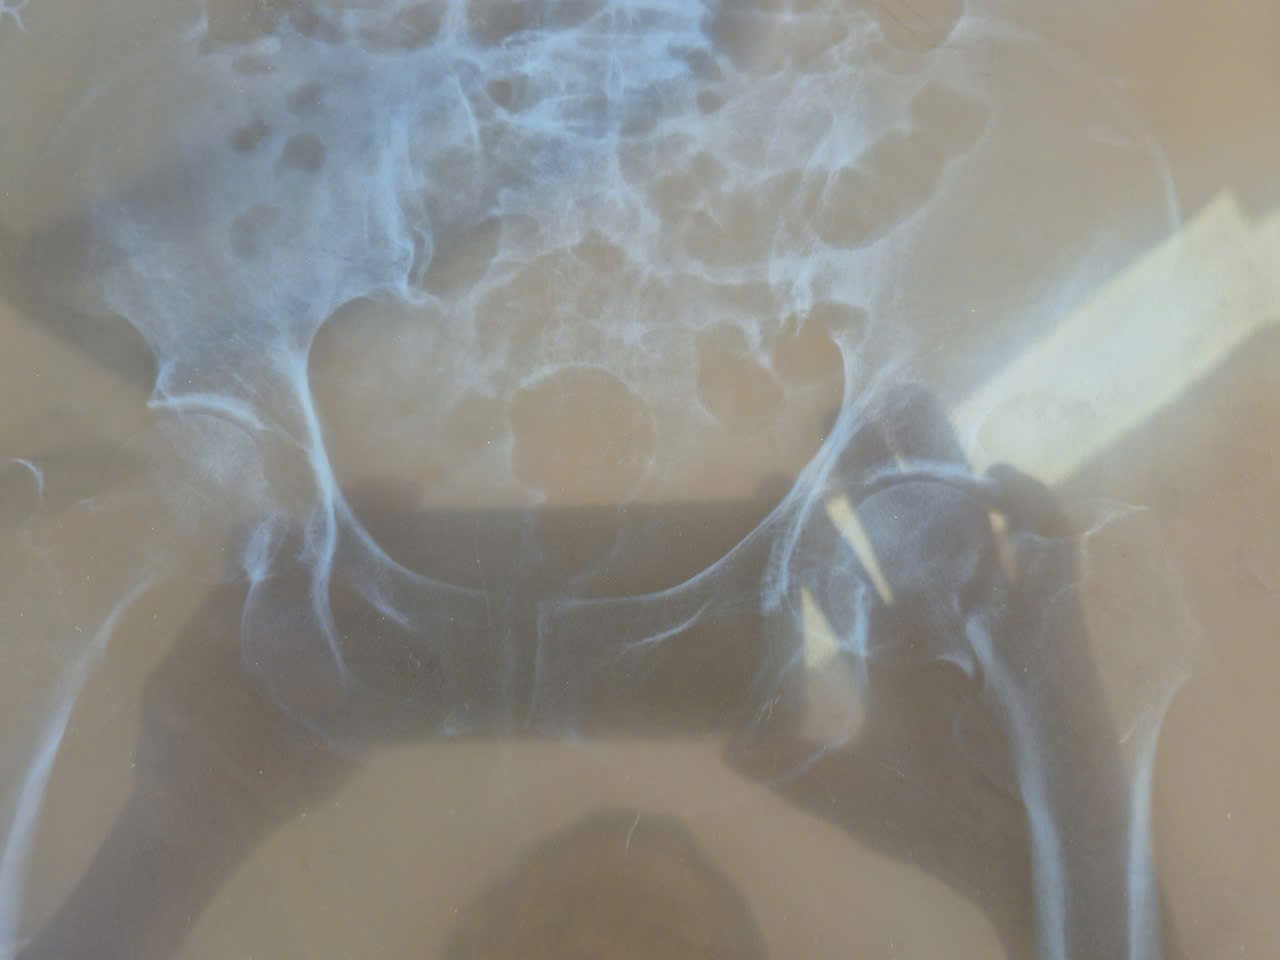

Bệnh nhân T. T. Đ. 94 tuổi xã Đề Gi, Gia Lai nhập viện ngày 10-12-2025. Vào viện vì sưng đau đùi trái sau tai nạn sinh hoạt. Khám lâm sàng ghi nhận; sưng đau đùi trái, mất vận động chân trái, bàn chân trái xoay ngoài. BN khó thở thường xuyên, tim nhanh, 2 phổi có ran. Cận lâm sàng gồm có: Xquang xương: gãy cổ xương đùi trái Garden IV. Siêu âm tim: Hở van 2 lá, giảm động vách liên thất, nhịp tim không đều, chức năng tâm thu thất trái giảm 42%. Điện tim đồ: thiếu máu cơ tim cục bộ mạn tính.

Trước bệnh cảnh trên tập thể khoa Ngoại nhận định đây là trường hợp gãy cổ xương đùi trái có chỉ định phẫu thuật để phục hồi chức năng vận động sớm, giảm đau cho bệnh nhân và tránh các biến chứng do gãy xương nằm lâu, hơn nữa bệnh nhân và gia đình có nguyện vọng tha thiết muốn phẫu thuật. Tuy nhiên BN rất cao tuổi, nguy cơ phẫu thuật cao, dễ xảy ra biến cố trong và sau mổ do đó cần sự phối hợp đa chuyên khoa. Một cuộc hội chẩn liên viện được tổ chức dưới sự chủ tọa BS Bành Quang Khải, Phó Giám đốc Trung tâm, bs Nguyễn Thành Phó khoa Gây mê hồi sức BVĐK TT tỉnh Gia Lai cùng bs khoa Ngoại, GMHS, HSTC của Trung tâm. Kết luận của hội đồng hội chẩn: Gãy cổ xương đùi trái Garden IV/ Viêm phổi-suy tim EF giảm-bệnh tim thiếu máu cục bộ có chỉ định thay khớp háng bán phần. Sau khi được điều trị nội khoa tích cực 3 ngày, BN được phẫu thuật với ekip gồm: BS Mang Đức Tiến Hoan, trưởng khoa Ngoại, phẫu thuật viên chính, BS Nguyễn Thành (BVĐKTT Gia Lai) gây mê chính cùng bs khoa Ngoại, Hồi sức cấp cứu. BN được thay khớp háng bán phần bipolar không xi măng. Cuộc phẫu thuật tiến hành trong vòng 90 phút, nhanh gọn chính xác, an toàn. Sau mổ được theo dõi sát tại khoa Hồi sức tích cực, từ ngày thứ 4, bệnh nhân bắt đầu tập đi với sự hỗ trợ của dụng cụ. Sau 8 ngày, Ekip phẫu thuật đánh giá tỉnh trạng lâm sàng ổn định, đã vận động đi lại chủ động với dụng cụ hỗ trợ, vết mổ lành, bệnh xuất viện trong niềm vui khôn xiết của bệnh nhân và gia đình.